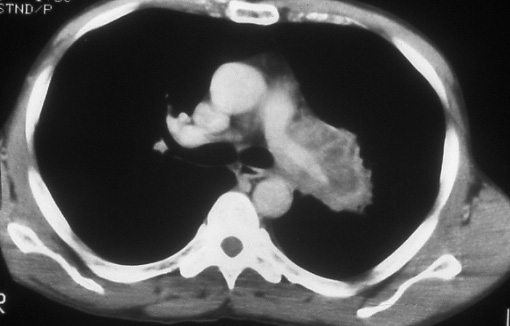

Fig. 16b: Computed tomographic scan of the chest shows that the tumor totally surrounds and compresses the left pulmonary artery and extends into the Intrapericardial portion of the vessel. Involvement of the Intrapericardial portions of the pulmonary arteries should be classified T4; tumor extension involving the vessels distal to the pericardium is T3. (see p. 53)